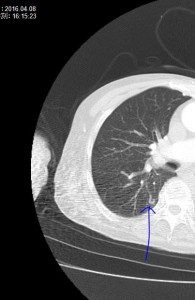

「肺動脈静脈瘻」について学びました。

肺炎も肺梗塞もないのに、著明な低酸素血症を呈します。

CT画像ではあまり目立たないクリっとしたコイルのような血管がみえます。血液ガスではシャントが存在するので、PO2、PCO2ともに低下します(A-aDO2が開大します)